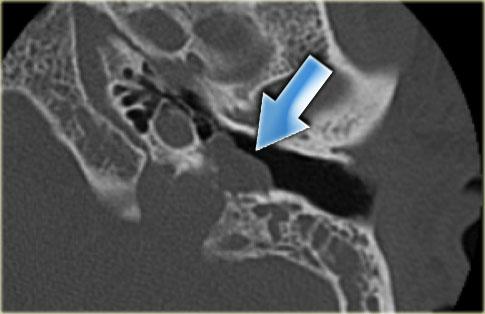

Bên trái là hình ảnh cắt ngang và cắt vành của một bệnh nhân nam 50 tuổi.

Phát hiện tình cờ túi thừa hành tĩnh mạch cảnh (mũi tên).